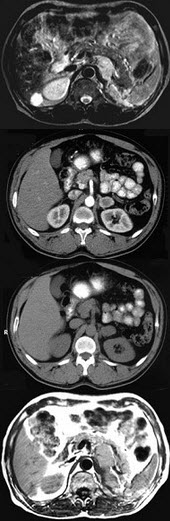

女,34岁,无意中发现血压升高4个月就诊,行CT检查,如图所示,下列说法正确的是( )

A:CT示左侧肾上腺区可见一等密度块影,边界清楚

B:增强扫描,该病灶周边明显强化,中心处强化不明显

C:考虑为左肾上腺腺瘤

D:考虑为左肾上腺嗜铬细胞瘤

E:考虑为左肾上腺转移瘤